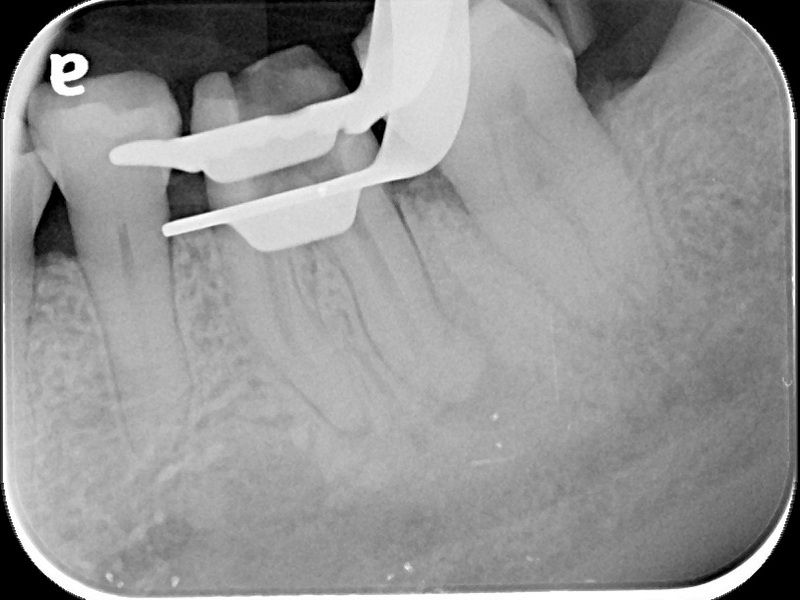

74歲的陳爺爺左下顎第一大臼齒處多年前曾接受根管治療,並裝上牙套,去年年中因為該處長了膿包,出現不適感,在坊間診所拆除舊牙套後,轉診來到台北慈濟醫院牙科部牙髓病科黃耀民醫師門診,希望在不拔牙的情況下解決膿包問題。透過X光及臨床檢查,黃耀民醫師發現膿包位在大臼齒頰側靠後方位置,且牙根底部有黑影表示有發炎狀況,左側根管內亦留存上次根管治療的分離器械。黃耀民醫師在顯微鏡視野下,利用超音波器械將根管內原有的馬來膠針封填物及分離器械移除,並徹底清潔根管系統,最後做緊密的封填。半年後回診,陳爺爺無任何不適,牙根尖的發炎狀況已經消失,膿包也未再出現,便返回原診所重做牙套。

根管治療是將根管系統做徹底的清創,藉由治療器械及殺菌藥水移除所有的牙髓組織及感染原,最後再用根管封填材料做緻密的充填,以維持清潔環境並減少病菌再次入侵感染的機會。黃耀民醫師提到,根管治療是為了增加保留牙齒的機會避免被拔除,但因為操作範圍狹小,且根管型態複雜多變,且可能還有根管彎曲、鈣化阻塞等現象,過去只能倚靠醫師臨床經驗及手感進行治療,容易有清創程度不足而導致治療效果不佳的現象。而牙科顯微鏡是現今輔助治療的新趨勢,可提供充分的照明及最大25至30的放大倍率,讓醫師更能看清楚根管系統,再搭配超音波器械,以最少破壞齒質的方式,做最大程度的清潔。一般而言,傳統根管治療的成功率約7至8成,而顯微鏡輔助根管治療的成功率可高達9成。

牙科顯微鏡除了適用於複雜型根管系統的治療外,在根管穿孔修補、根管內分離器械移除、齒裂檢查、活髓治療等方面都扮演重要的角色。另外,在根尖手術或牙周病手術時若能搭配顯微鏡,則更能有效清除掉肉眼不易看見的發炎感染組織,提高治療的成功率。牙周病科蘇穎珊醫師也表示牙科顯微鏡也是牙周治療的新利器,除了可以精細觀察牙周病灶以及精確找到致病因子進行有效的清潔,在手術治療上藉由放大設備可以進行微創治療減小傷口,縮短癒合期,提高治療的效率。